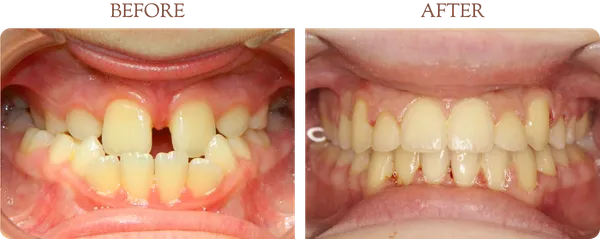

Real Patient Results

Smile Transformations

Every smile tells a story. Browse our gallery of real before-and-after results from patients treated by Dr. Thomas J. Griffin.